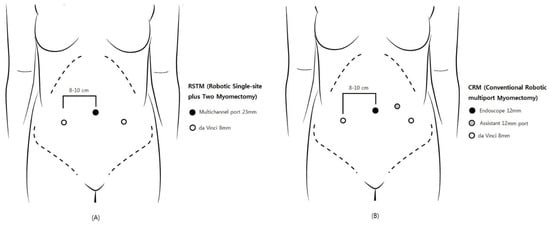

In 2004, Advincula et al. reported the first conventional robotic multi-port myomectomy (CRM) [3], and three later studies detailed favorable surgical outcomes [4,5,6]. For CRM, four incision sites, including the 12-mm camera port at the umbilicus, two 8-mm side ports, and a 12-mm or 5-mm laparoscopic assistant port, are required. Robotic single-site myomectomy (RSSM) has been introduced to minimize surgical injury by reducing the number of ports; however, many studies have reported problematic issues due to inherent technical problems, such as limited traction with semi-rigid instruments, as well as range-of-motion limitations [7,8].

Robotic single-site plus two-port myomectomy (RSTM) was designed to reduce the number of incision sites while retaining the advantage of CRM. The RSTM apparatus includes a 23-mm multi-channel single port at the umbilicus and just two 8-mm side ports, without CRM’s additional assistant port. Through the multi-channel single port at the umbilicus, the 12-mm robotic camera and the laparoscopic assistant instrument are inserted.

RSTM by the da Vinci Si or Xi robotic system (Intuitive Surgical, Inc., Sunnyvale, CA, USA) was performed. A 23-mm incision established the single-site port of entry at the umbilicus. Subsequently, the glove port (Nelis, Seoul, Korea), followed by the 12-mm camera port (at the umbilicus) and the two 8-mm side ports were inserted (Figure 1A and Figure 2). The remaining port site of a glove port was used for assistant laparoscopic instruments. Once all of the trocars had been inserted, the surgical cart was docked vertically. Monopolar curved scissors were wielded in the right arm, and bipolar forceps in the left. A diluted vasopressin solution (0.25 U/mL concentration) was infused into the myoma. The monopolar curved scissors in the right robotic arm made the incision, while the forceps in the left arm applied counter-traction. V-loc™ (Covidien, Dublin, Ireland) was utilized for multiple-layer suturing of the uterine wall, and in-bag scalpel morcellation was performed to retrieve the myomas through the umbilical incision.

Figure 1.

Comparison of trocar placement: (A) robotic single-site plus two-port myomectomy (RSTM); (B) conventional robotic multi-port myomectomy (CRM).

2.1.2. CRM

CRM was performed using the da Vinci Si or Xi robotic system. The 12-mm camera port at the umbilicus, the two 8-mm side ports, and the 12-mm assistant port were inserted (Figure 1B). The subsequent procedures were the same as in RSTM, except for the morcellation method: that is, in CRM, the myomas were retrieved by electric power morcellation.